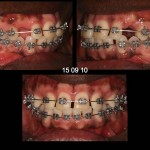

Foto e documentazione